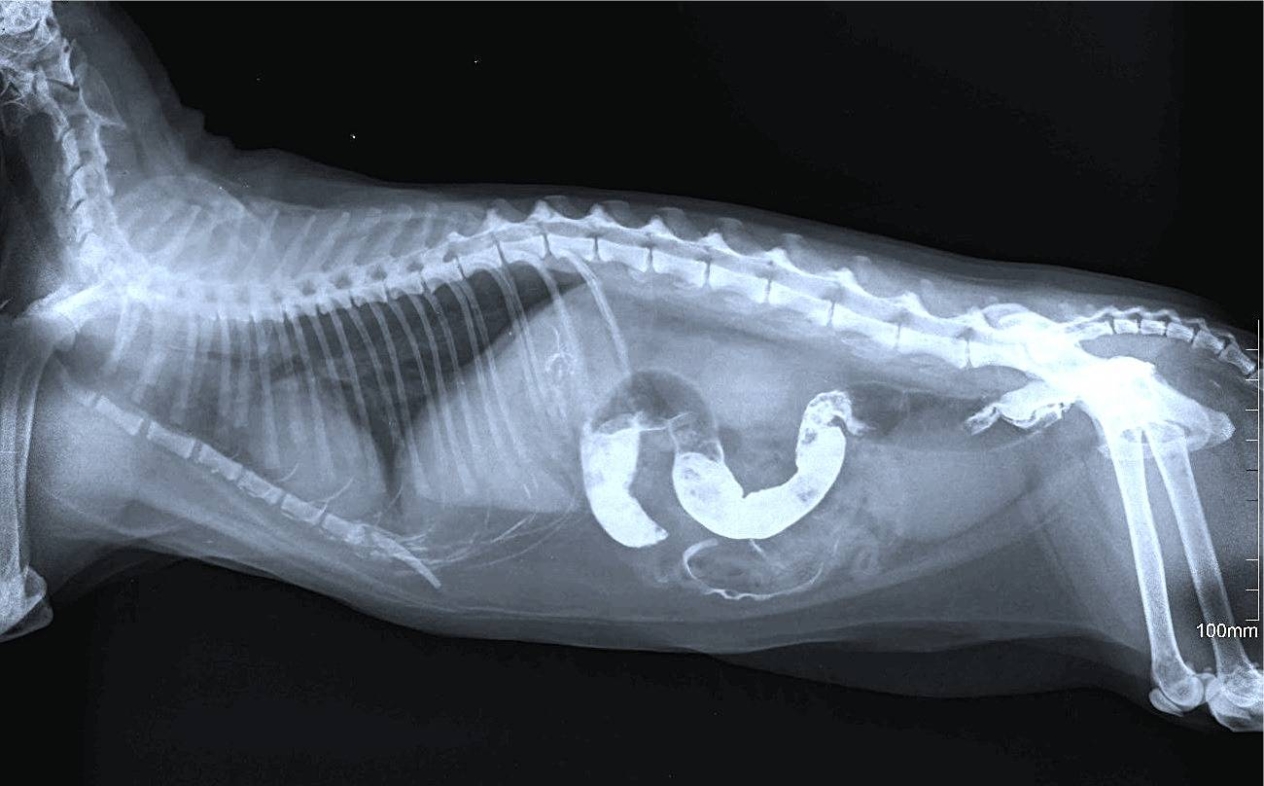

Eine Magendrehung (Torsion) ist ein akuter und sehr gefährlicher Zustand, der bei Hunden großer Rassen mit tiefem Brustkorb häufiger vorkommt. Nach aktivem Spielen oder schnellem Fressen dehnt sich der Magen durch Gas oder Nahrung aus und dreht sich dann um seine Achse. Infolgedessen wird die Blutzufuhr unterbrochen und das Organ beginnt abzusterben.

So sieht das aus:

– Der Magen schwillt schnell an und wird sehr hart;

– der Hund speichelt, versucht zu erbrechen, aber ohne Erfolg;

– das ängstliche Verhalten geht in eine Depression über.

Dies ist eine Notfallsituation. Sie können nicht warten – Sie müssen sofort zum Tierarzt gehen. Jede Minute zählt.